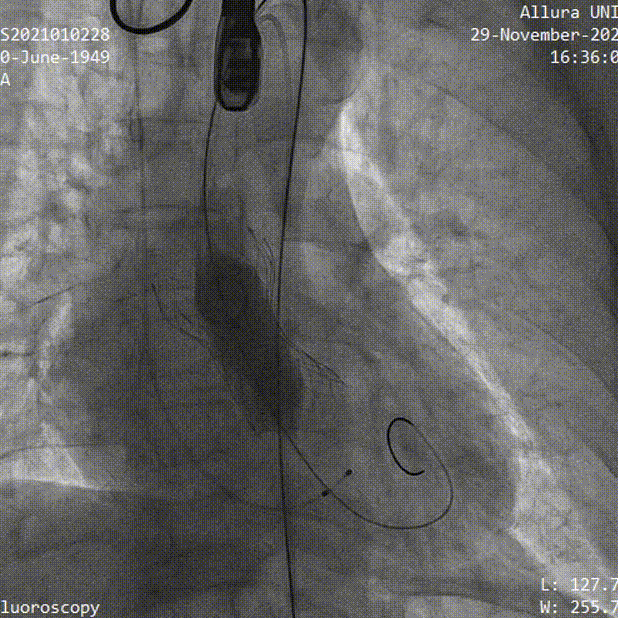

主动脉根部造影

23mm球囊预扩

瓣膜定位

瓣膜释放

球囊后扩

术后造影